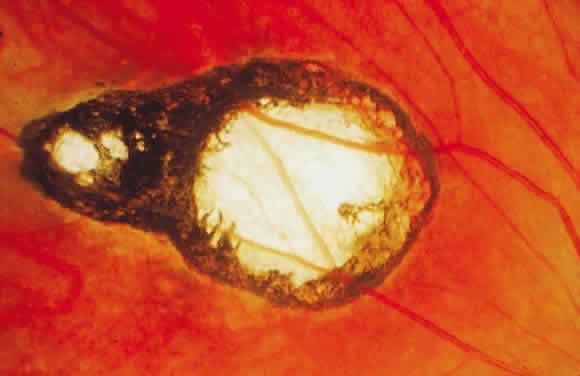

Bradyzoites are slowly metabolizing organisms found in cysts formed within the tissue of the infected host. The size of the Toxoplasma cyst varies, depending on the number of organisms that have multiplied within it. The cyst may reach more than 100 μm in diameter and may contain from 50 to 3000 organisms. The cyst wall is strongly argyrophilic and periodic acid-Schiff positive. It contains constituents that are derived from both the parasite and the host tissue. Constituent from the host tissue compose the outer part of the cyst, whereas those derived from the parasite are in the inner part of the cyst wall. Toxoplasmosis may be found in the inner layers of the retina after episodes of acute retinochoroiditis. The cyst may stay in the retinal tissue for years without showing any signs of invasiveness. Considering that the tissue cyst incorporates elements derived from the host into its outer wall, it is easily tolerated by the host, and no inflammatory reaction is seen around it (Fig. 2). It may remain for years in certain tissues, such as the eye or muscles, without provoking any inflammatory reactions. The bradyzoite inside the cyst derives its nutrition from the slow diffusion of substances through the cyst wall. The number of organisms increases within the cyst in the retina, and once the cyst wall breaks down by mechanical stretching, the bradyzoites escape, convert into tachyzoites, and invade contiguous cells. This process may lead to recurrence of retinitis. Certain immunologic mechanisms of the host may influence the organisms significantly. Immunosuppression coinciding with the rupture of the cyst and release of bradyzoites allows the organisms to become tachyzoites and proliferate in host tissue without restriction. The cyst of the Toxoplasma organism appears to be a defensive stage in its life cycle. The resistance of toxoplasmosis within chronically infected tissues of animals may lead to transmission of the disease by the ingestion of undercooked meat, including mutton, beef, pork, and chicken. Tissue cysts can develop within any organ and are commonly found in infected tissues of brain, eye, heart, skeletal muscles, and lymph nodes. Rupture of tissue cysts causes reactivation of the systemic toxoplasmosis in immune deficiency states, leading to dissemination of Toxoplasma organisms to other organs.